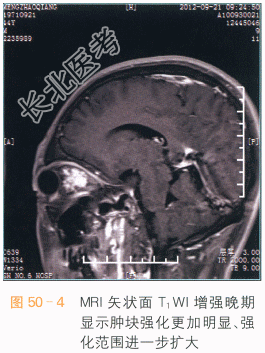

眼眶海绵状血管瘤CT表现为肌锥内类圆形边界清楚之占位,软组织密度,可见结节状钙化,注入造影剂后,呈渐进性强化,为该病的特征表现。肿块占位效应较轻,肿块较大时眼外肌受压向外侧移位,眼球向前方突出。MRI检查时,病灶的T₁WI信号和肌肉类似如图50-1所示,若有血栓形成,可表现为不规则高信号,T₂WI呈类圆形高信号,内偶可见细小低信号分隔,周围假包膜呈低信号,通常没有囊变或坏死如图50-2所示。MRI多平面扫描可以清晰显示肿块的边界,其与视神经、眼球、眼外肌分界清楚,见渐进性强化如图50-3、图50-4所示。